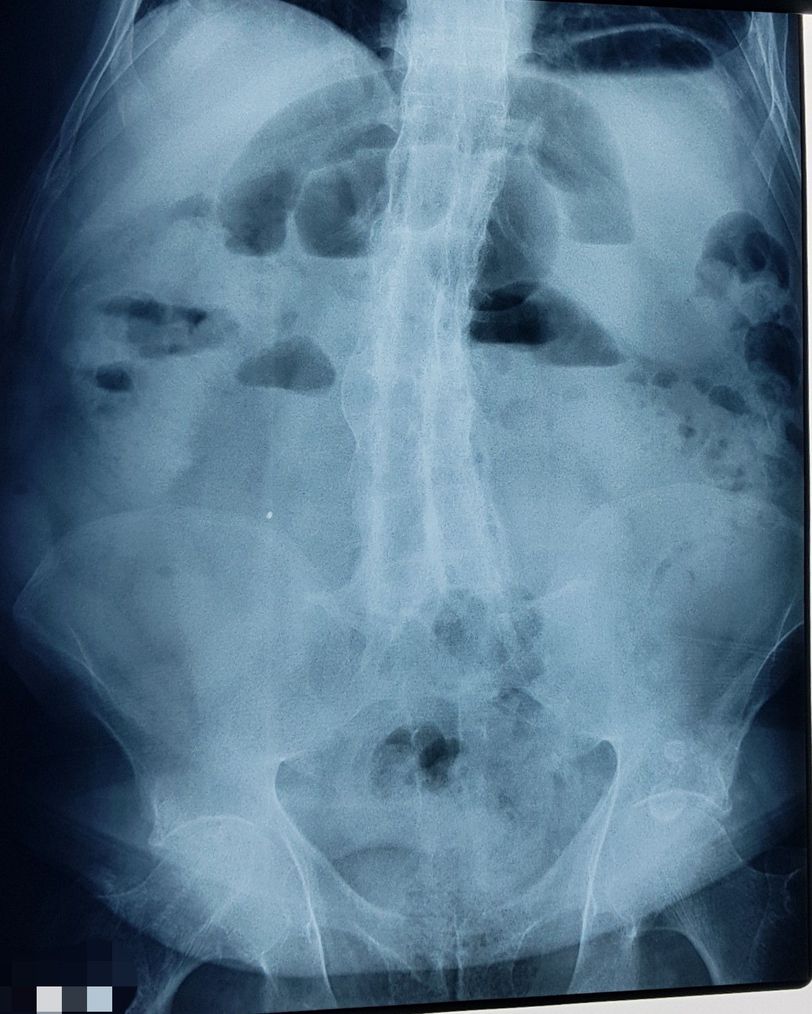

An 82 year old man with a history o crohn dissease with an evolution of 20 year, treated with steroids and inmunotherapy. Likely controled until he arrives because he had an exacerbation. In the INCMSZ told him they dont have beds so he came to my service. Oh Surprise, he have had an exacerbation but i present to you a "melt candle image" in the AP projection. The correct name of This dissease its Diffuse idiopathic skeletal hyperostosis. 1 case in every 500,000 patients, 25 reports so far.